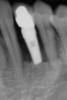

Figure 7  Radiograph of residual ridge defect in site No. 22.

Figure 7

The patient had no medical concerns and had a history of an implant placement in December 2002 when she was 25 years old. In February 2005, she presented with a mobile implant and an associated advanced peri-implantitis. Radiographic review at the initial examination demonstrated significant destruction of the dentoalveolar ridge around the implant as well as around the adjacent natural dentition. Emergency-based treatment involved surgical implant removal only and debridement of the infection (Figure 4 and Figure 5). Following uneventful healing, an advanced ridge defect was apparent at the edentulous site and moderate and advanced attachment loss noted at No. 22D and No. 21M, respectively (Figure 6 and Figure 7). This case demonstrates bone loss of two separate origins: lack of bone because of tooth agenesis and destruction of bone from inflammatory peri-implantitis.